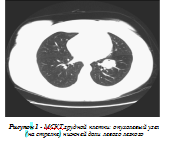

Другие легочные поля обычные. Дважды была проведена бронхоскопия и установлено, что левый нижний долевой бронх сужен опухолевидным образованием, содержит слизь, слизистая оболочка сохранена. МСКТ грудной клетки: в нижней доле левого легкого определяется округлое образование 35х32 мм, не отграниченное от корня; 8 и 9 сегментарные бронхи сужены (рис.1). Заключение: КТ -картина рака нижней доли левого легкого. Цитологическое исследование бронхоальвеолярного смыва: слизь, группы клеток призматического эпителия; раковые клетки не выявлены; общее количество клеток в смыве 0,05х10х6/л: лимфоциты - 4%, нейтрофилы - 74%, альвеолярные макрофаги - 22%.